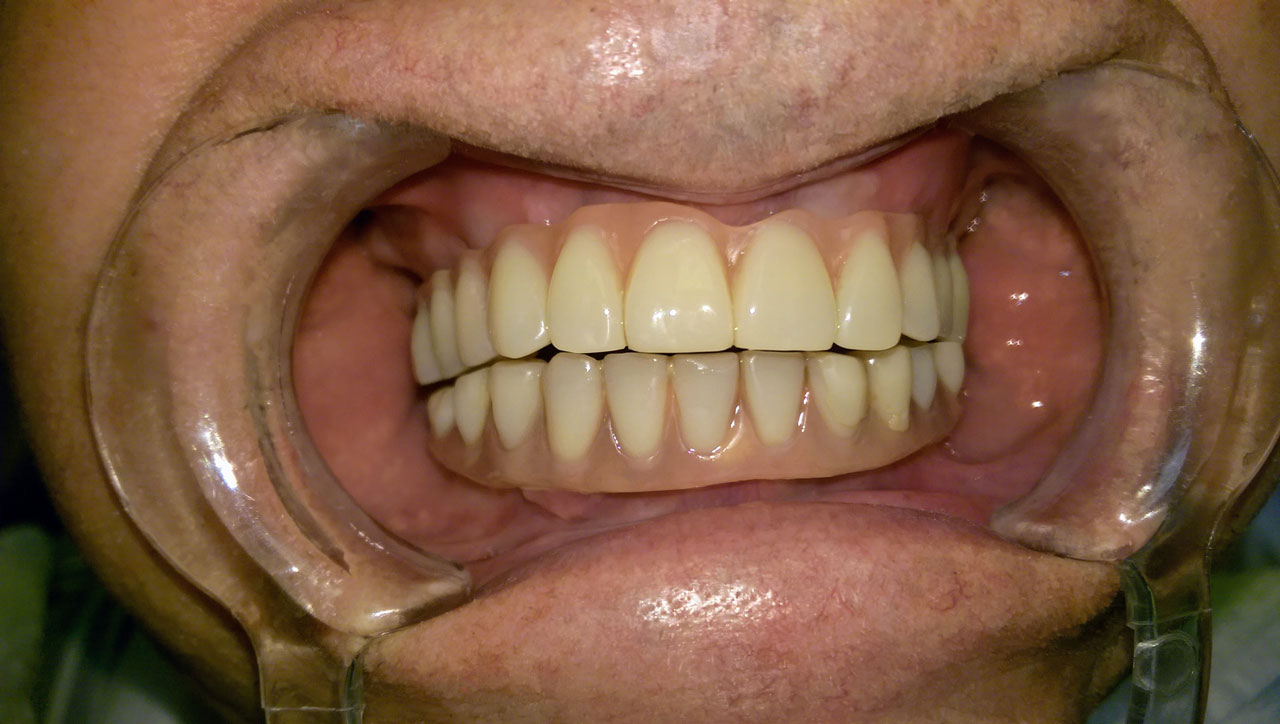

Teljes szájüregi rehabilitáció két lépésben

Ismét egy teljes szájüregi rehabilitáció két lépésben. Először az alsó fogak lettek kihúzva és azonnal implantálva, híddal ellátva, majd később a felső. IHDE svájci azonnal terhelhető implantátumok és cirkónium hidak. Dr. Kelemen Péter és a Symbion Fogtechnika közös munkája.